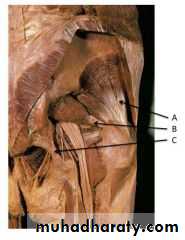

Practical Anatomy of The Lower Limbs for 1st Year Students

Prof.Dr.Abduljabar Alhubaity

Dep.of Anatomy/College of Medicine

University of Mosul